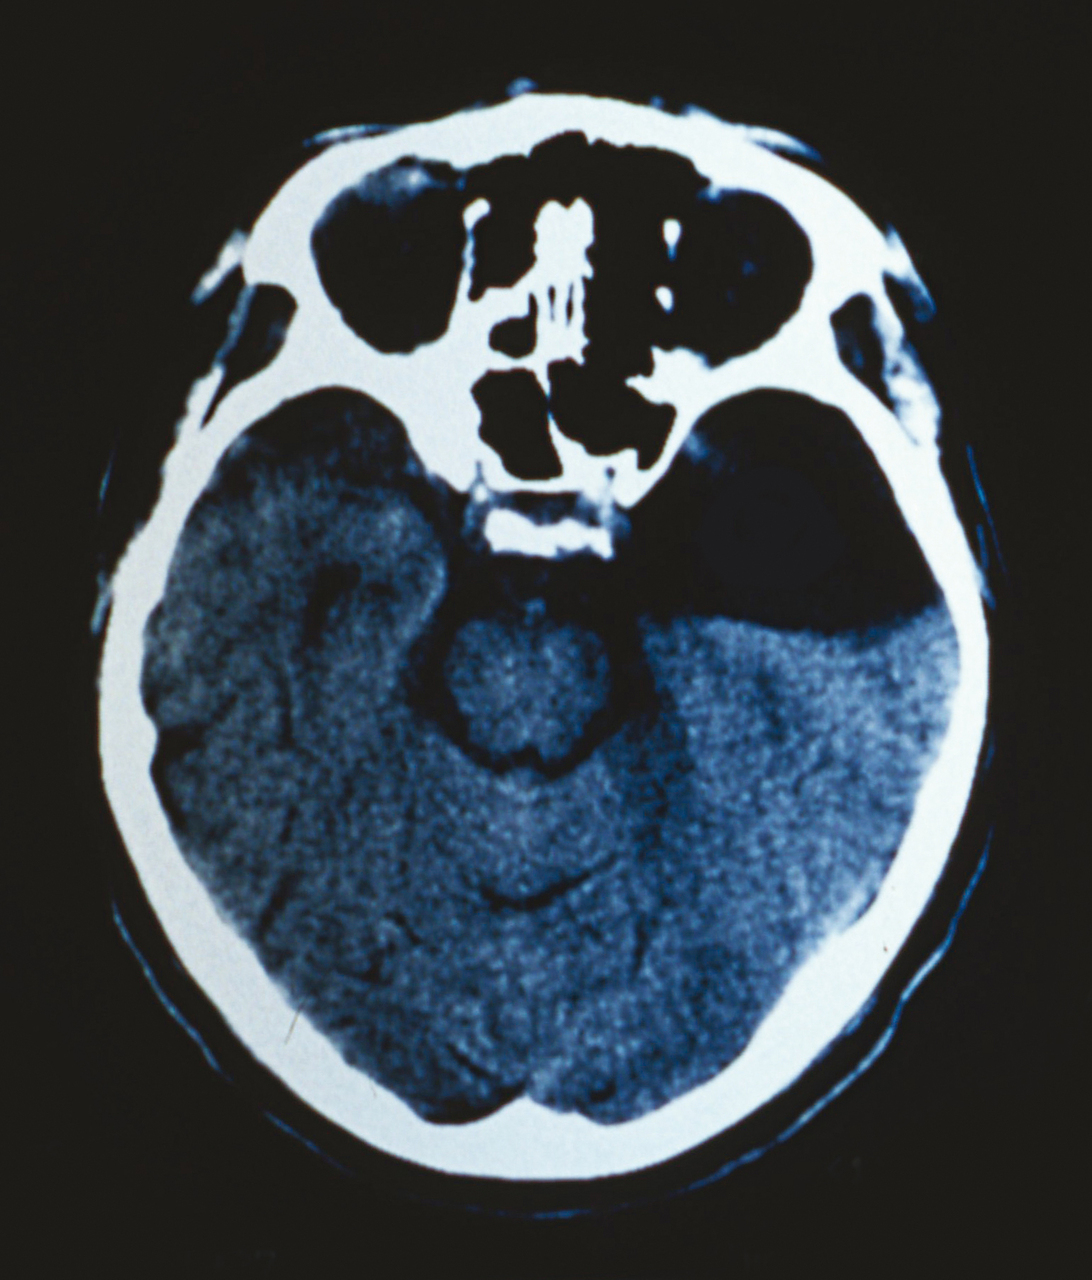

Quel est votre diagnostic ?

Il s'agit d'un kyste arachnoïdien. Les kystes arachnoïdiens sont des accumulations de liquide céphalorachidien à l'intérieur de la membrane arachnoïdienne. Ils sont le plus souvent supratentoriels, la localisation temporale étant la plus fréquente. Environ 1 % des kystes entraînent des symptômes essentiellement neurologiques (céphalées, crises convulsives, troubles neurocognitifs, ataxie, hydrocéphalie) et parfois endocriniens. Un traitement n'est proposé qu'en cas de signes cliniques. La dérivation kystopéritonéale isolée est la technique la plus employée